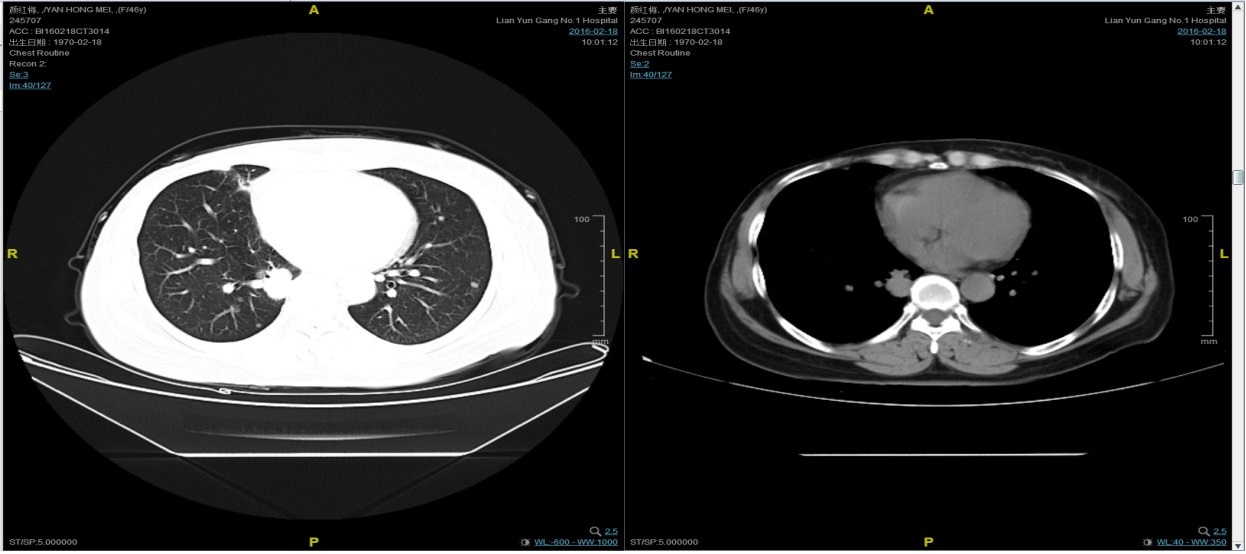

随访至2016-2-18,肺部病灶进展,肺内转移病灶增多。PFS2=10个月。

三线解救治疗及评价

从2016-2-19开始给予紫杉醇+曲妥珠单抗治疗,紫杉醇240mg,3周重复,曲妥珠单抗330mg三周重复。患者末次应用曲妥珠单抗和紫杉醇时间为2016-6-24,紫杉醇共应用4周期。